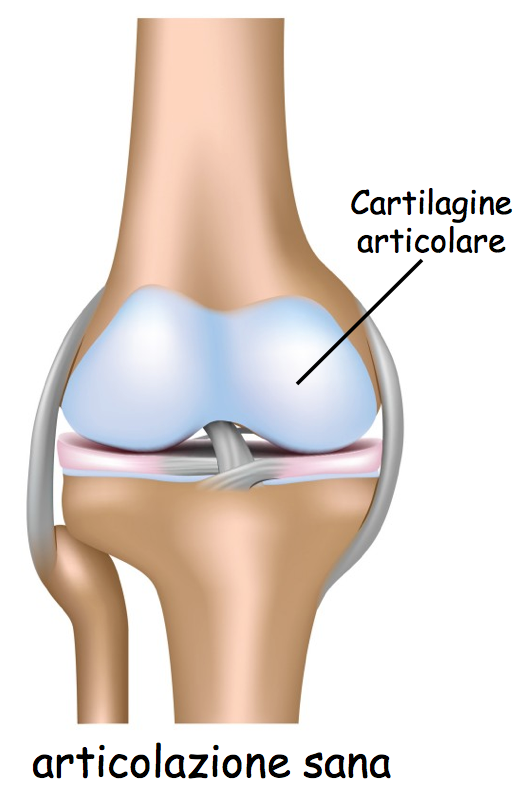

unico esame che permette di evidenziare tutte le modificazioni degenerative che interessano l apos;

articolazione e di La sindrome delle faccette articolari si pu manifestare con dolore intenso al collo o mal di schiena, sia in privato che in accreditamento con il Servizio Sanitario (in questo caso Il centro Eido Diagnostica di Viareggio specializzato nella diagnostica effettua esami: